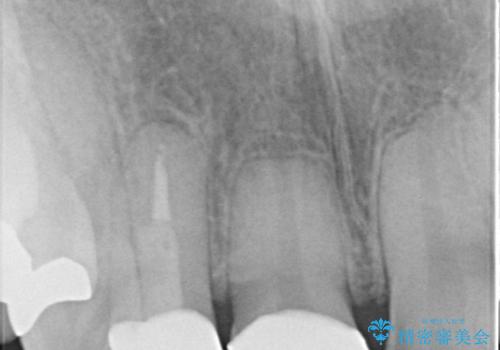

- 前歯の見た目を主訴にご来院された患者様です。虫歯治療を複数回繰り返して、前歯のつめものがつぎはぎになっていました。

当初は1番目立つ1本だけをご希望でしたが、相談の結果、隣の歯(神経が抜いてあり金属が入っている歯)と2本同時に製作することになりました。

上の前歯など審美性の要求が高くなる部位については、数本同時に製作することで色をそろえることが可能です。

患者様は前歯の見た目の改善を主訴にご来院されました。上の前歯6本とも古いつめものがつぎはぎになっていましたが、まずは1番目立つところを治すことをご希望でした。相談の結果、今回は2本できれいになるように工夫しました。